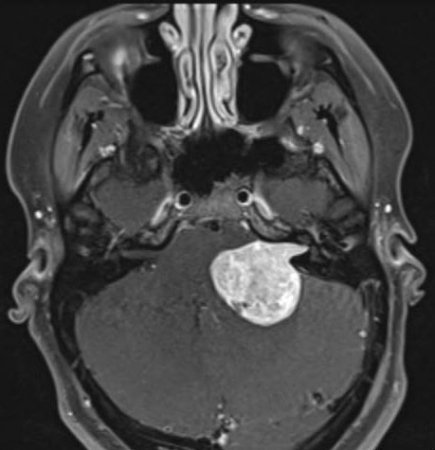

听神经瘤是起源于神经膜细胞的良性肿瘤,主要发生于听神经的前庭支(下图)。少数情况下,肿瘤直接来自脑神经Ⅷ的听攴。面神经的神经膜细胞肿瘤如果位于脑桥小脑角时,与听神经瘤很...